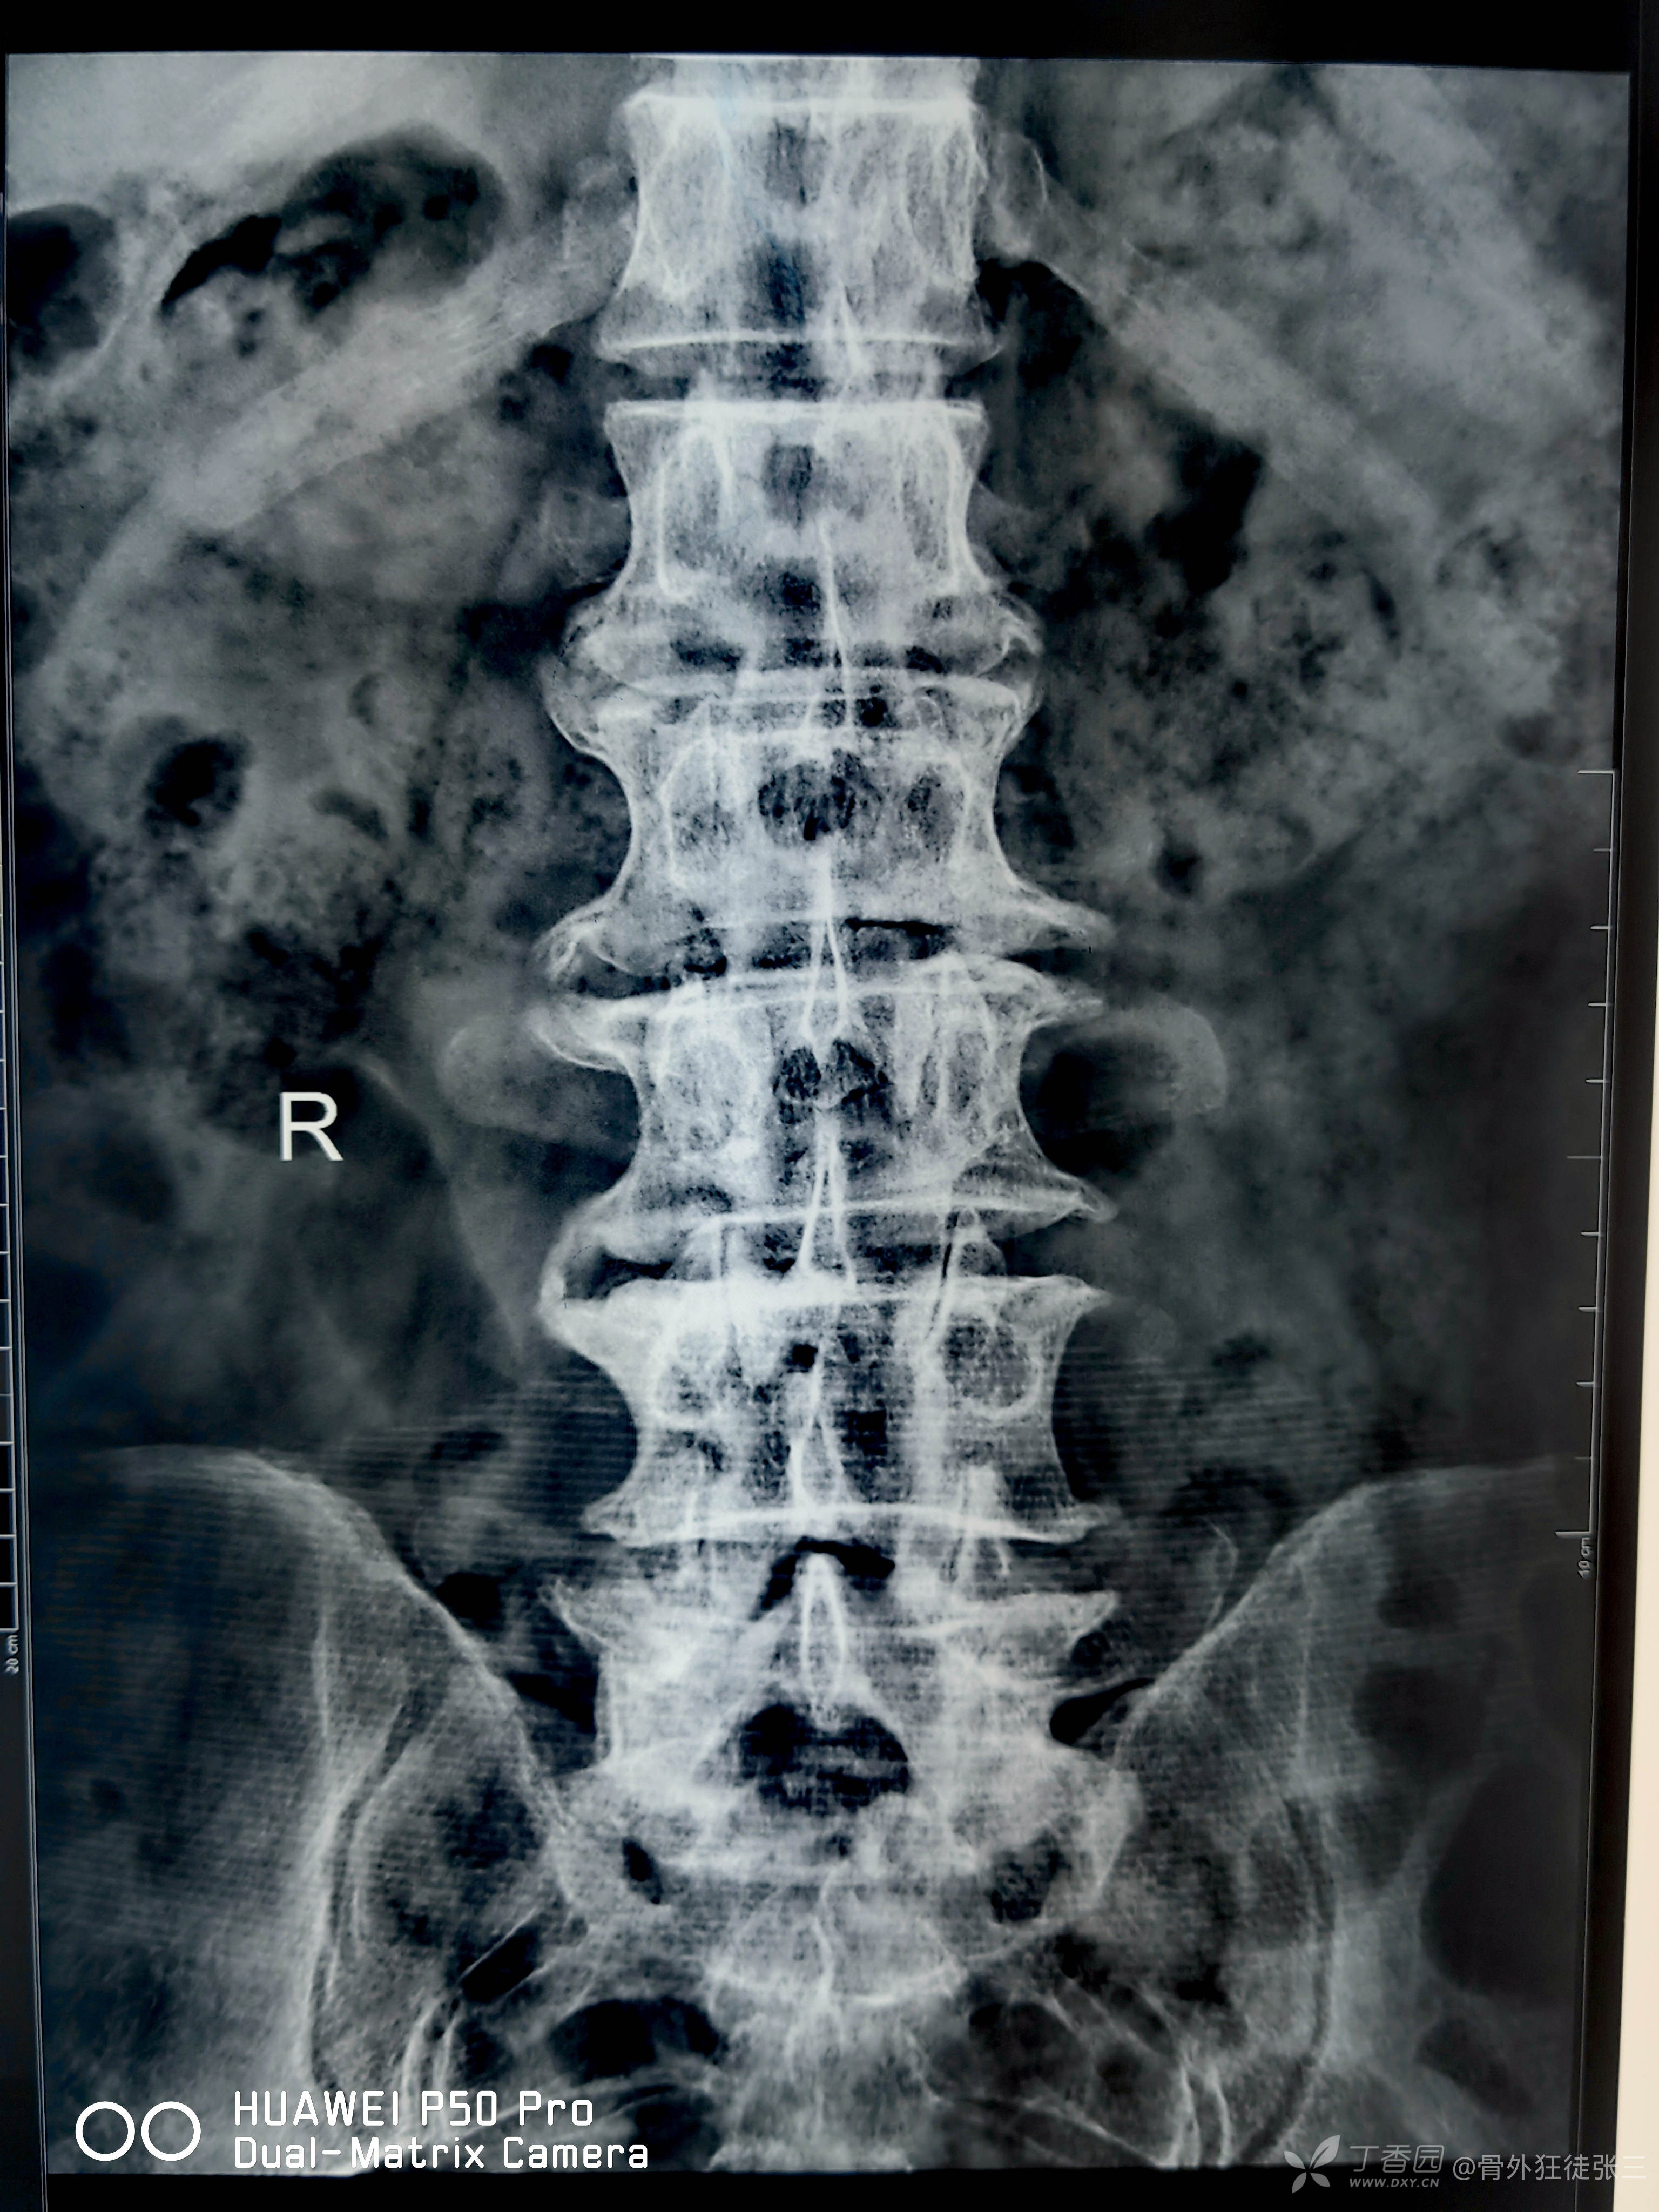

病例学习:发育性腰椎管狭窄——“站着说话也腰疼”

L陈云旗 等 5 位达人已点赞患者性别:男

患者年龄:63岁

主诉:腰疼伴双下肢放射疼20年,加重伴间歇性跛行2年。

简要病史:20年前劳累后出现腰疼伴双下肢放射疼,休息后可缓解,间断保守治疗,效果欠佳,近2年上述症状加重,行走100米左右即出现跛行,休息后症状缓解不明显,卧床时双下肢麻木、疼痛加重,久站、久坐时症状加重。

辅助检查: